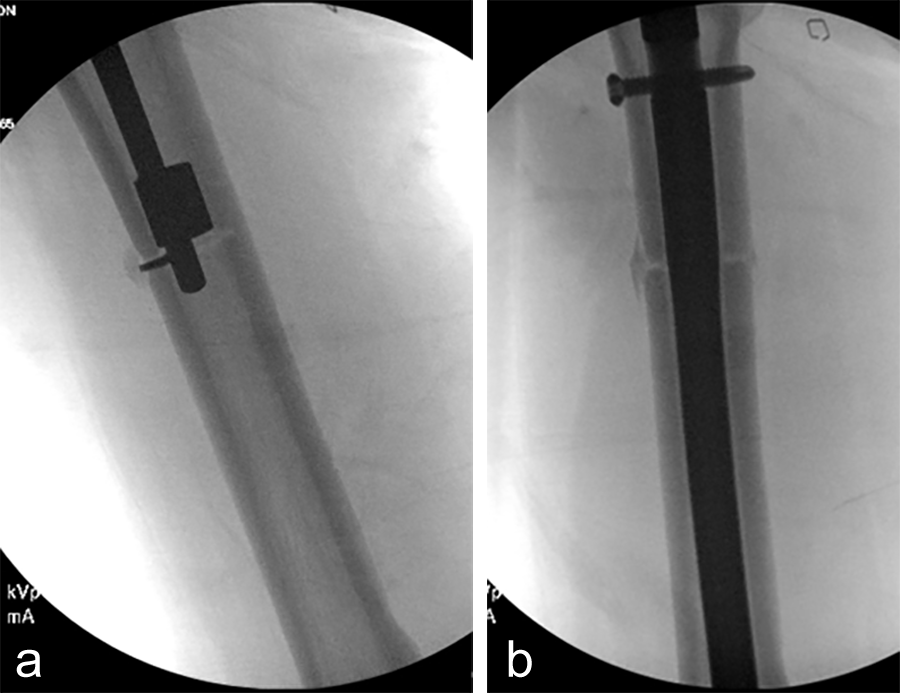

The treatment plan was to remove the femoral intramedullary (IM) nail, to perform a derotational osteotomy of the femur with an internal saw, and then to refix the femur with a new antegrade IM nail.

The tibial deformity was planned to be managed with a MAXFRAME AUTOSTRUT™.